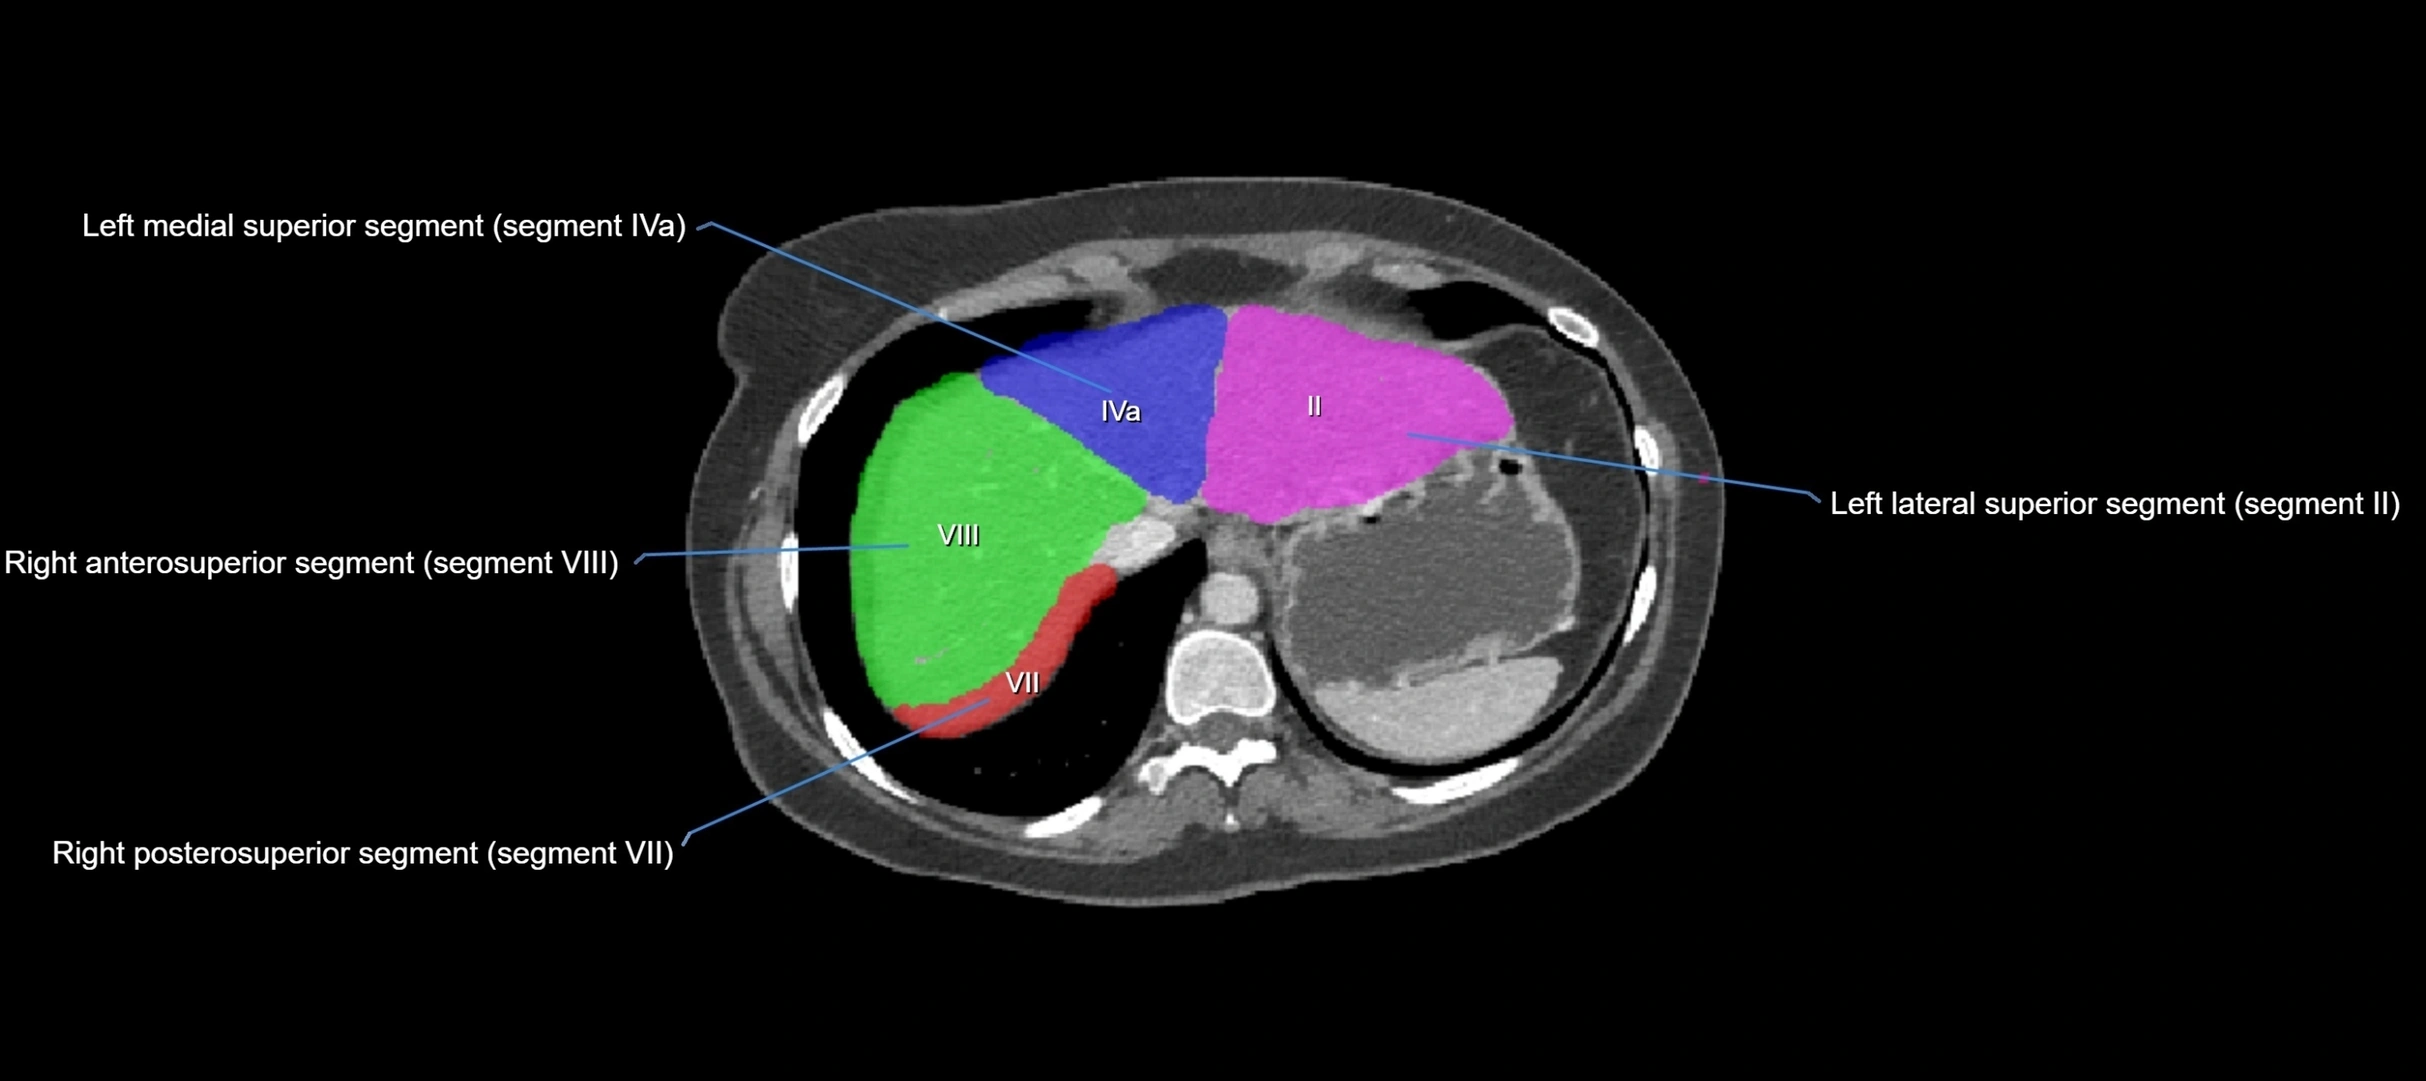

CT Image

image